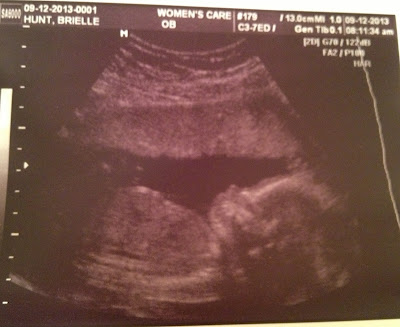

So the moment you have all been waiting for, or if you are like me you just skipped to this part in the first place... the pictures! And sorry for the crappy picture of a picture look, our printer is broken so I couldn't scan in the pictures.

Isn't he just the cutest thing you have ever seen?

Can you see his hands up by his face? sooo cute!

Look at that spine!

This is the ultra sound our first doctor gave us. We had a gender reveal party so the doctor didn't tell us what we were having. This is what he gave us in the envelope. The diagram was on the back of this picture, it's supposedly a mirror image but once again all I see is a blur.